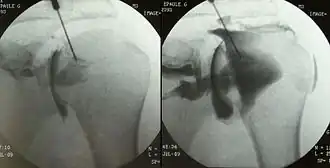

An arthrogram is a series of images of a joint after injection of a contrast medium, usually done by fluoroscopy or MRI. The injection is normally done under a local anesthetic such as Novocain or lidocaine. The radiologist or radiographer performs the study using fluoroscopy or x-ray to guide the placement of the needle into the joint and then injects around 10 ml of contrast based on age. There is some burning pain from the anesthetic and a painful bubbling feeling in the joint after the contrast is injected. This only lasts 20 – 30 hours until the Contrast is absorbed. During this time, while it is allowed, it is painful to use the limb for around 10 hours. After that the radiologist can more clearly see what is going on under your skin and can get results out within 24 to 48 hours.

Shoulder arthrography can be used to study tears of the rotator cuff, glenoid labrum and biceps.[2] The type of contrast injected into the joint depends on the subsequent imaging that is planned. For pneumoarthrography, gas is used, for CT or radiographs, a water-soluble radiopaque contrast, and for MRI, gadolinium. Double-contrast arthrography can be used for more anatomically complex cases, though its use is relatively infrequent. The needle is radiographically guided into the glenohumeral joint space, after which the patient is evaluated by fluoroscopy, CT or MRI. The gadolinium in the contrast fluid yields a bright signal on T1 weighted images allowing for better evaluation of the joint capsule, the articular surface of the bones and, in particular, the labral cartilage. MR arthrography is most often used in evaluation of the hip and acetabular labrum, of the shoulder rotator cuff and glenoid labrum, and less often in the wrist.[2] Arthrograms can be diagnostic and therapeutic. Therapeutic arthrograms often distend the joint with cortisone and lidocaine, with a common site being the shoulder. Diagnostic arthrograms can be direct, as described above with penetration of the joint, or indirect, by a venous injection of contrast material and delayed imaging with CT or MRI.[2]